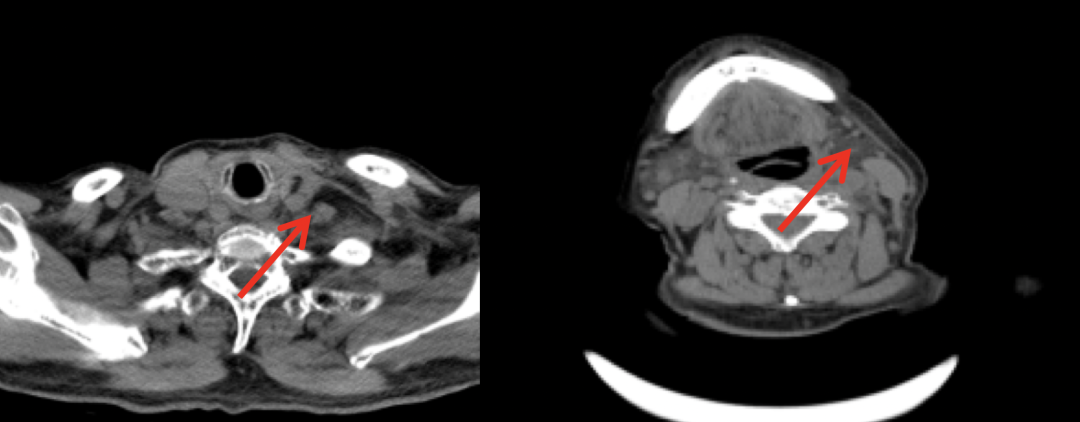

影像检查

图片

2020年1月3日影像学示左侧颈部肿块大小约4.5cm